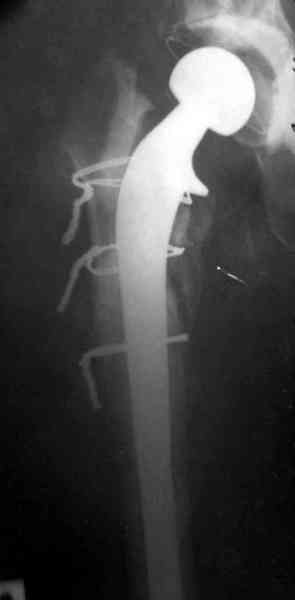

Представляю вашему вниманию снимки (прошу прошения за качество снимков) больной 48 лет с ревматоидным артритом, которой был сделан тотальный эндопротез справа,

контрольный снимок сделали только на 21день после операции (№1) и с интервалом 5 дней второй снимок (№2)

Судя по всему, произошел раскол наружной стенки бедра и ножка находится вне костного канала. В таком случае

решение одно - удаление ножки и установка новой в расчете на дистальную фиксацию. Конктреную модель подсказать тяжело из-за низкого качества Р-грамм.

№3-6 снимки с осложнением